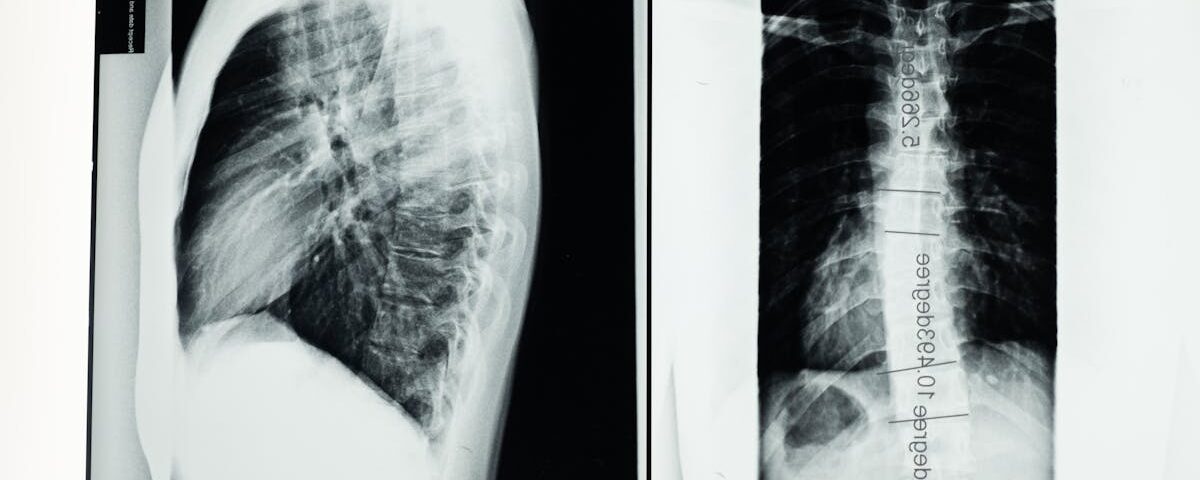

Quels examens permettent de diagnostiquer une hernie discale?

Une IRM ou une radiographie est utilisée pour confirmer le diagnostic d’une hernie discale.